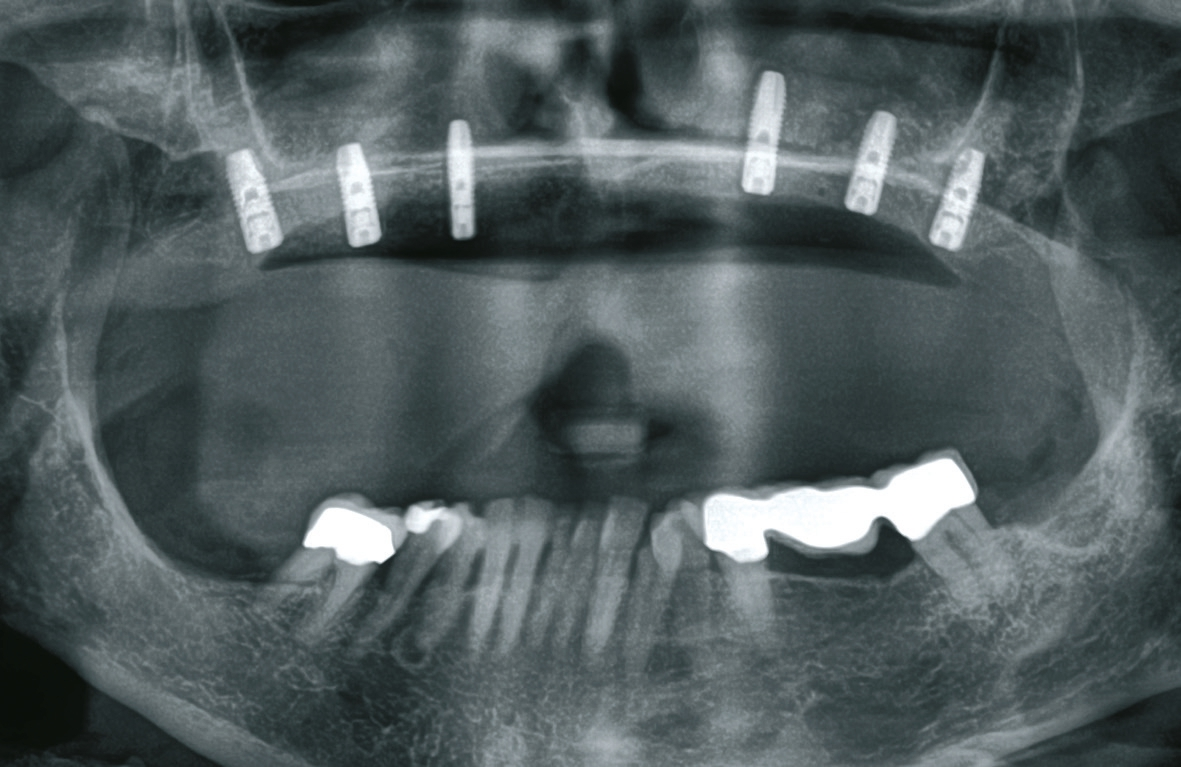

Vor dem zweiten OP-Eingriff nach 4 Monaten wurde im Labor eine Bohrschablone hergestellt. Zudem wurde ein DVT angefertigt, um im Sinne eines backward planning die idealen Implantatpositionen zu ermitteln. Bei Eröffnung des augmentierten Kieferbereiches zeigte sich eine gute Regeneration und Revaskularisierung des Knochens. Sechs Implantate konnten mit ausreichender Länge und passendem Durchmesser so in den augmentierten Bereich (Astratech EV®, Dentsply Sirona Implants, Mannheim) inseriert werden, dass sich eine gleichmäßige Pfeilerverteilung ergab (Abb. 7 u. 8).

Rückblick

Großvolumige Knochendefekte stellen chirurgische und prothetische Herausforderungen an den implantologischen Behandler [2,14]. Im vorgestellten Fall erfolgte die Therapie der ausgedehnten Knochendefekte im Oberkiefer nach dem „biologischen Konzept“ nur mit autologem Knochen. Nach der Schaffung eines suffizienten Knochenangebotes wurden die Implantate in möglichst gleichmäßiger Verteilung inseriert, um ein gutes Unterstützungspolygon für die Prothetik und damit eine gute Kraftverteilung zu erreichen.